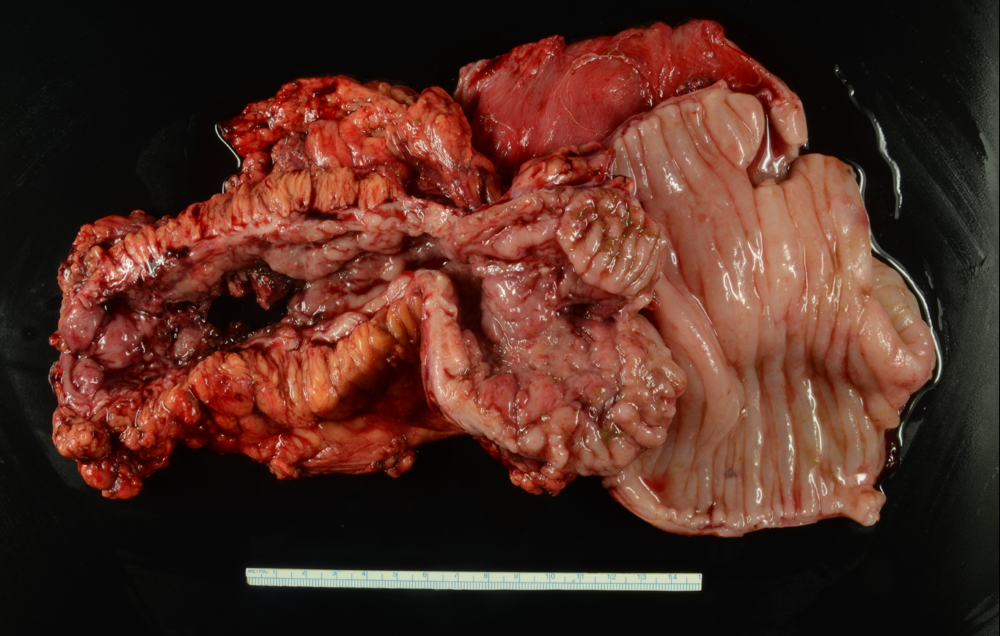

Gross description

Gross images

Contributed by Elizabeth Heidi Cheek-Norgan, M.H.S., PA (ASCP) and Catherine E. Hagen, M.D.

Stricture Stricture

Stricture

• Colon, resection:

• Severely active chronic colitis with transmural inflammation and fissuring ulcers compatible with Crohn's colitis; no dysplasia or malignancy